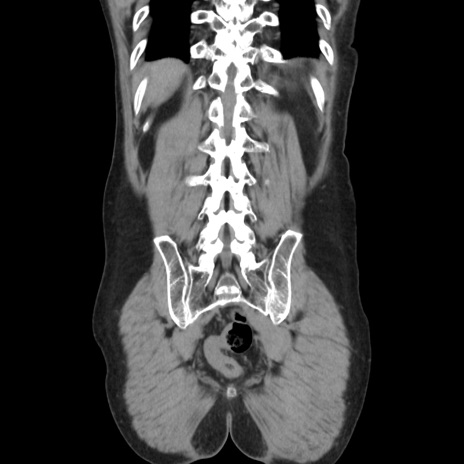

症例37(冠状断像)

【症例】40歳代 男性

【主訴】腹痛

【現病歴】4時間ほど前に電車に乗車中に臍部上より腹痛出現。徐々に増悪し起立困難となり、救急外来受診。生ものは数日食べていない。今朝お雑煮を食べた。

【身体所見】BT 36.8℃、BP 117/84mmHg、HR 91/min、SpO2 97%、苦悶様、腹部:臍上部広範囲圧痛あり、反跳痛±

【データ】WBC 8100、CRP 0.03